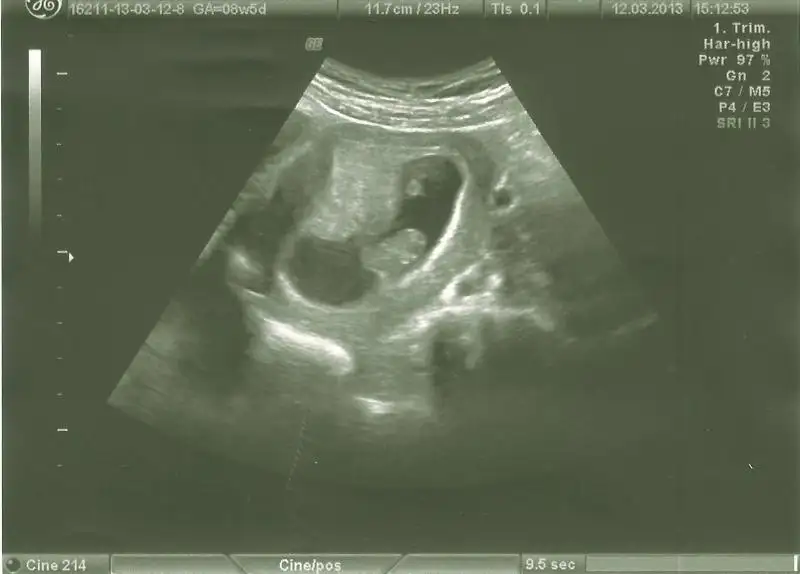

dr soylemeden siz gorun genital nub teorisi ( bebegin cinsiyeti)

bnde yorum bkliyorum kızlarr 2ncisi 11hafta bitiminde 2li tst günüydüü lütfeen

canim bu haftalarda paralel olup erkek cikan cok olduu simdilik paralel seninki 12 13 haftada bu skeil olsaydi kesin kiz derdim ama 11 haftada yorum yapamiyorum

evet bana da paralel geldi.dr da o hafta kıza benziyo dedi .ben 3.kıza hazırlıyorum psikolojimi.bir ihtimal belki rahat bir gebelik olması ve erkek belirtileri vermesi belki erkektir dedirtiyo ama nub ortada.

teoriye göre bakınca paralelse kız dikse erkek diyoruz ama ben bacaktan hiç ayırd edemiyorum bu nubu yahu...